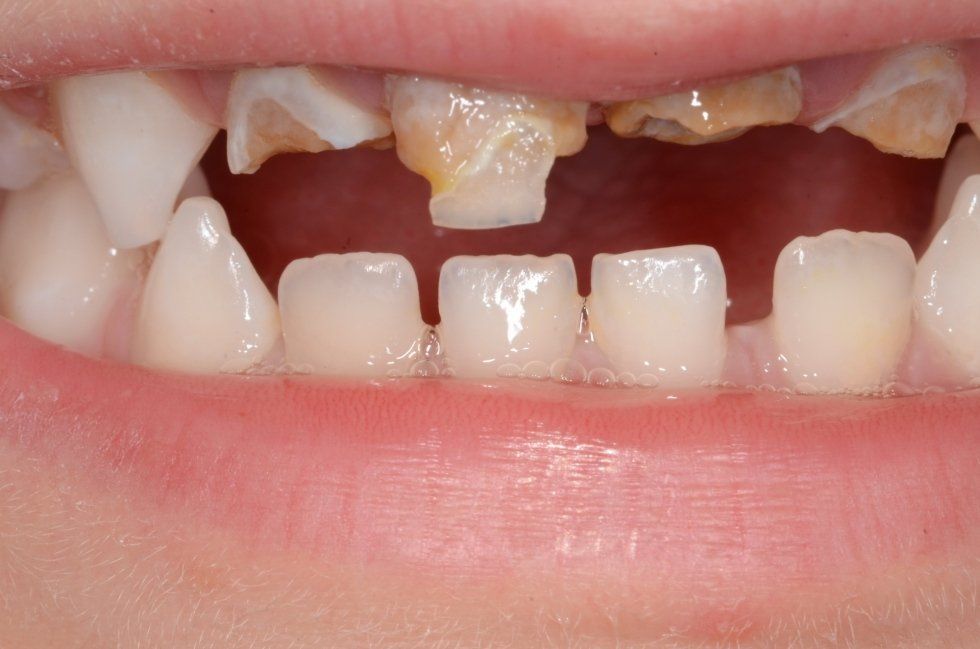

La carie nel bambino è una delle principali cause, insieme all’ortodonzia, di richiesta di intervento del dentista. La patologia ha una evoluzione particolarmente rapida in virtù della scarsità di smalto a difesa del dente da latte. Ciò comporta che, dal momento in cui il dente si ammala a quello in cui ne viene coinvolta la polpa (ovvero il nervo), il tempo sia veramente poco (vedi anche endodonzia pediatrica).

Spesso i dentini da latte cominciano a cariarsi già appena erompono nel cavo orale in quanto sono frequentemente a contatto con zuccheri semplici, come quelli veicolati dal biberon. Particolarmente aggressivi per i denti da latte risultano: tutte le tisane/infusi in commercio in bustine già pronte e pre-zuccherate; il latte zuccherato con qualsivoglia tipologia, incluso il miele; il latte e biscotti, specie nell’uso notturno; l’utilizzo quotidiano, spesso al posto dell’acqua, di succhi di frutta o bevande acide, per citare alcuni fra i più comuni errori commessi nel tentativo di dare una alimentazione completa al bambino, che spesso si traduce nella comparsa di una patologia chiamata